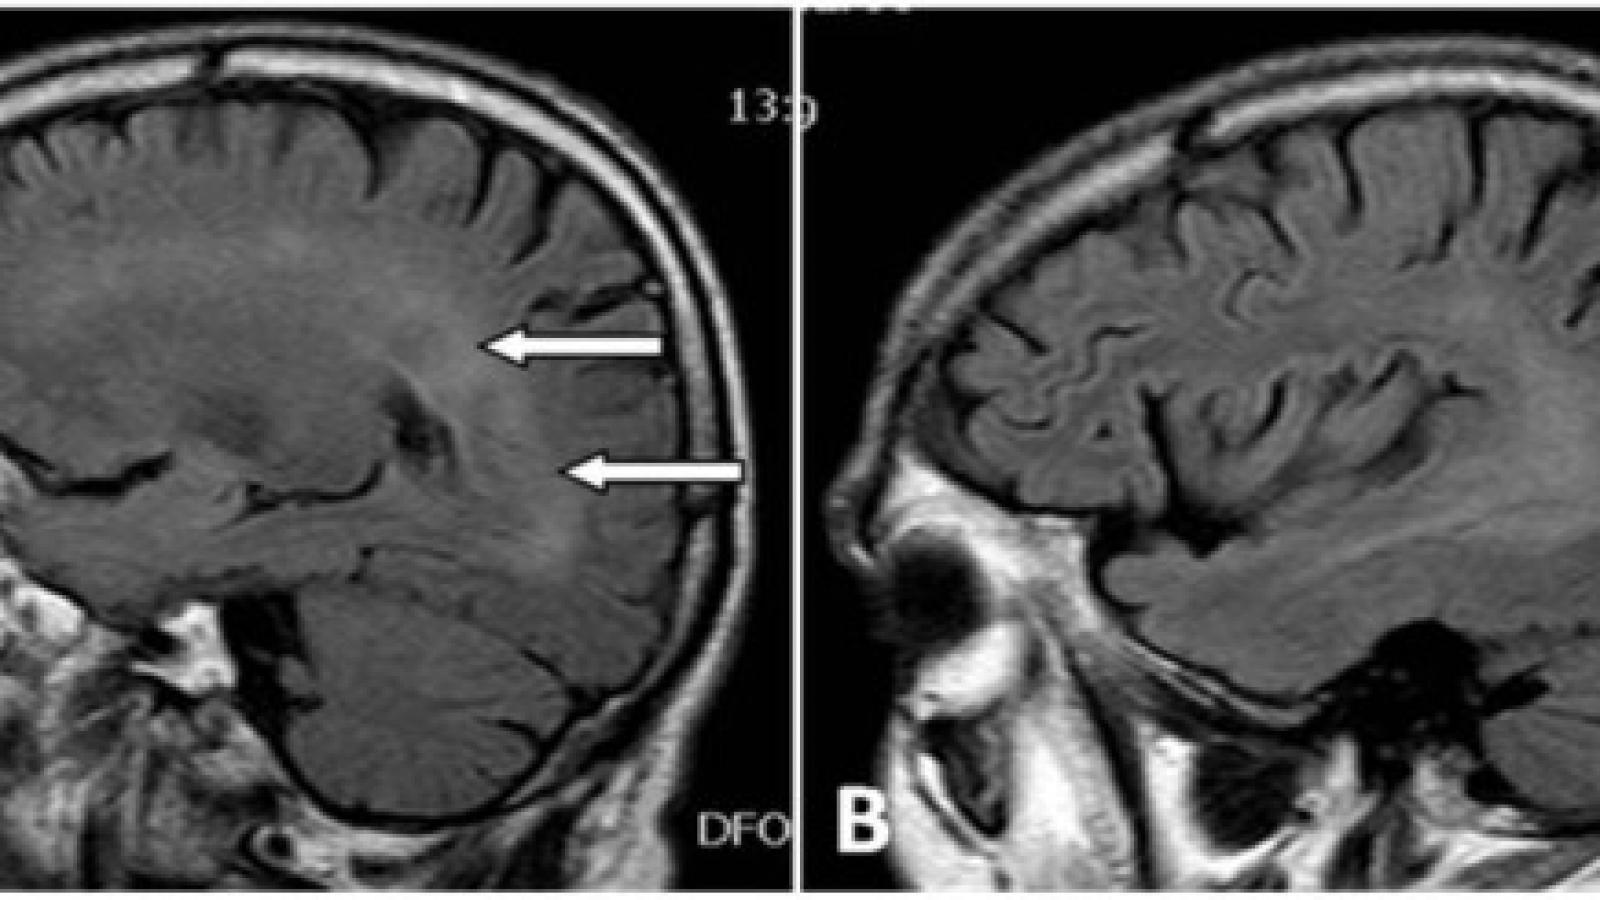

Large vessel vasculitis (LVV) and CNS vasculitis are rare subsets of vasculitis. The challenges related to these diseases are well known to the rheumatologists who treat around the world. There are many articles stating that a delay in diagnosis of these diseases leads to increased morbidity and mortality.